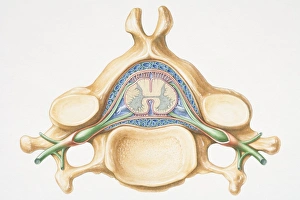

The central nervous system, the intricate network that governs our every thought and movement, is a marvel of complexity. From the delicate cerebellum tissue to the detailed light micrograph capturing its essence, we are reminded of its importance in maintaining balance and coordination. Anatomy comes alive as we explore the human brain from an inferior view. The intricacy of brain fibers is revealed through DTI MRI scans like C017/7099 and C017/7035, showcasing their vital role in transmitting information throughout this extraordinary organ. Artistic renderings bring us closer to understanding the medulla oblongata's significance within the brain. Its portrayal in various artworks allows us to appreciate how it controls essential functions such as breathing and heart rate. As we delve deeper into studying the central nervous system, models of the human brain provide invaluable insights into its structure and organization. Lateral views reveal countless regions responsible for cognition, emotion regulation, sensory perception, and motor control. Microscope slides offer glimpses into nerve cells' intricate architecture—a testament to their ability to transmit electrical signals at lightning speed. Meanwhile, glial stem cell cultures captured under a light microscope remind us of their crucial role in supporting neuronal function. Finally, artistic representations unveil the limbic system's enigmatic nature—an interconnected web responsible for emotions and memory formation. These captivating artworks allow us to visualize this complex network within our brains. Exploring these hints provides a glimpse into the awe-inspiring world of our central nervous system—the very foundation upon which our thoughts, actions, memories reside—reminding us just how remarkable our brains truly are.